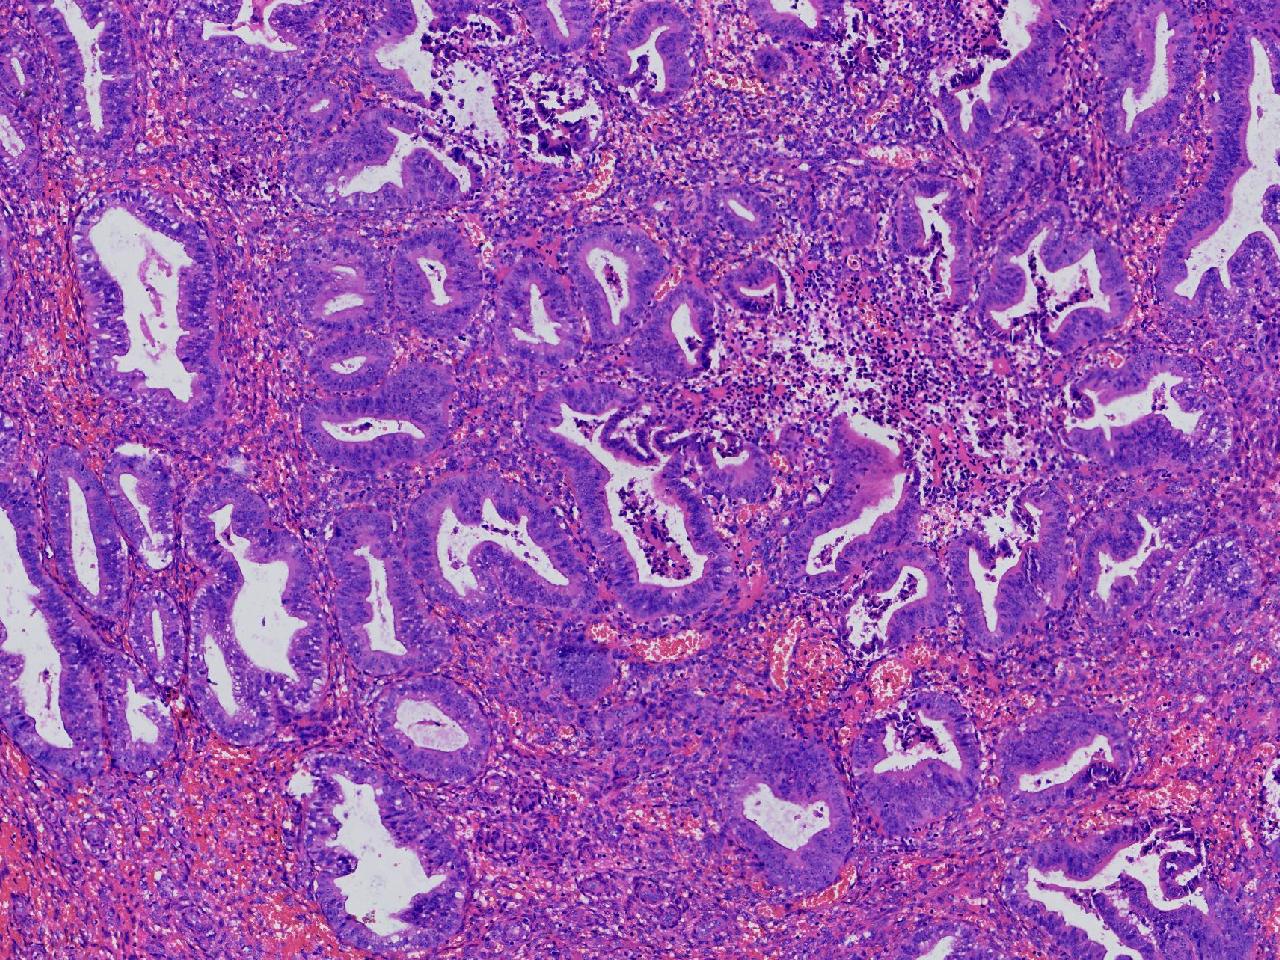

请教。1.有没有非典? 2.内膜是什么变化?

女,50岁,彩超示:粘膜厚度1.1cm。宫腔可见数个高回声,提示宫腔息肉。

子宫内膜+内膜息肉

灰粉色不整形软组织多块,3X3X2厘米。

子宫内膜息肉。

没有非典。

无非典型性子宫内膜增生,子宫内膜息肉

无非典内膜伴息肉。